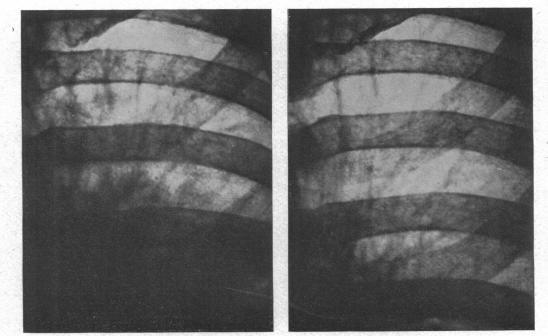

The radiology of acute pulmonary oedema.

Br Heart J. 1951 Oct;13(4):503-18. doi: 10.1136/hrt.13.4.503.